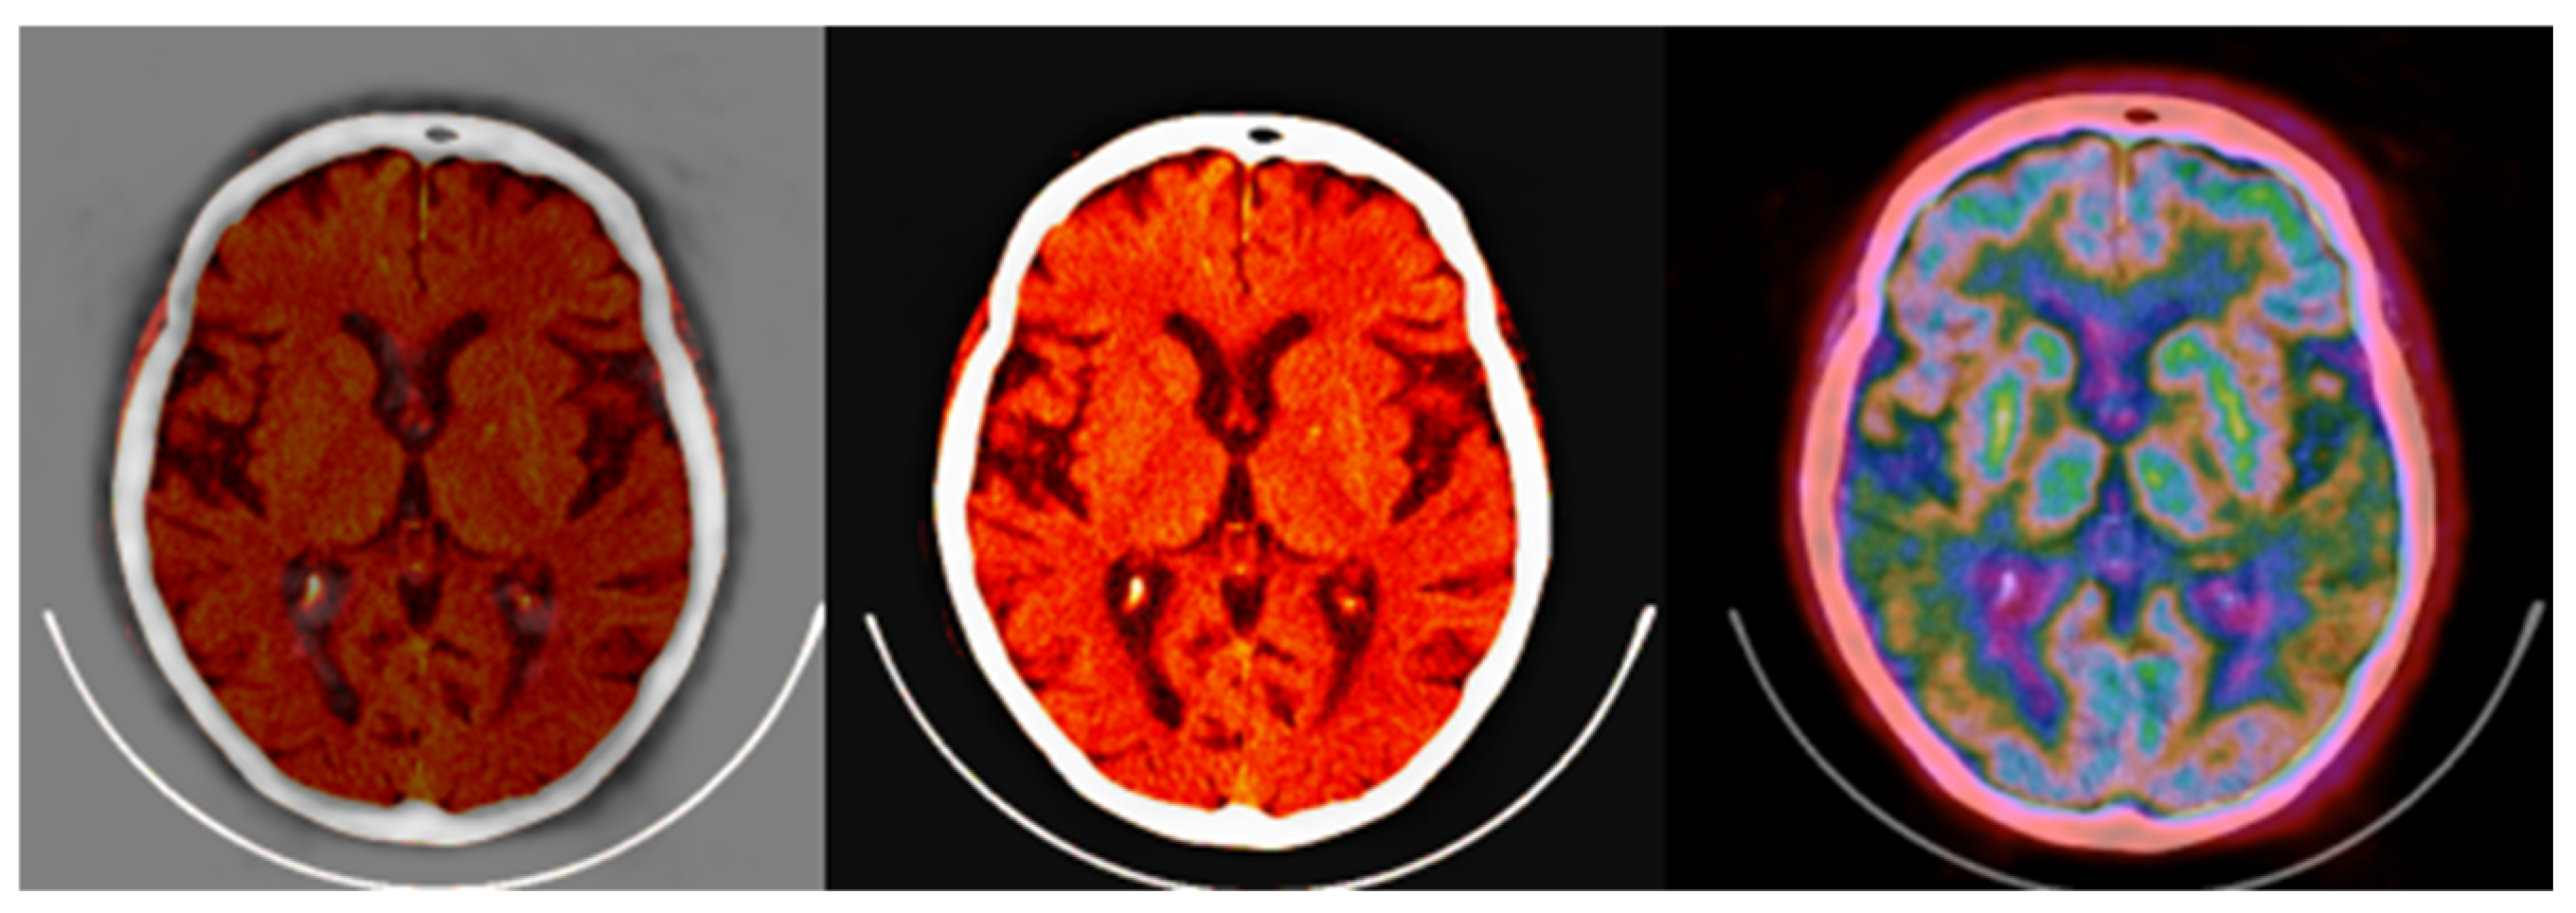

The fused images obtained with the proposed colormap folding may be compared with standard PET/CT fused data available on all manufacturers’ clinical workstation–user interfaces. Figure 15 presents typical results obtained for our data from a standard clinical interface and compares them to the fused image in Figure 14.

Figure 15.

(left,middle) images were obtained from a verified and clinically used PET/CT DICOM viewer software and represent the classical PET/CT fusion that may be used in clinical practice. These results may be compared with the 3-fold PET/CT fusion of Figure 14 using the proposed methodology.